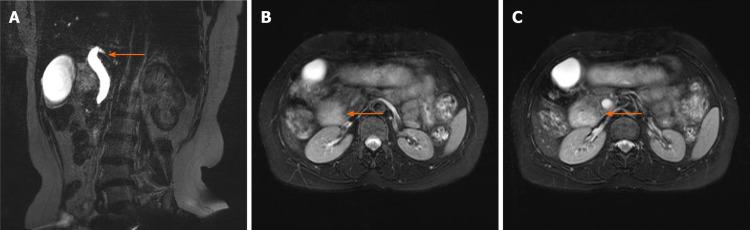

This study investigated the clinical manifestations, imaging features, complications, and treatment of six patients diagnosed with AP at the Department of Hepatobiliary and Pancreatic Surgery, First Hospital of Jilin University from January 2010 to June 2020. There were four males and two females, with an average age of 56.00 ± 9.86 years old. In this study, abdominal pain and jaundice were the main clinical manifestations. Imaging can show the "crocodile jaw sign" or "double bubble sign".

For patients with duodenal or biliary obstruction, physicians should give priority to AP when imaging examinations suggest that the duodenum is wrapped with tissue similar to the density of the pancreas. Symptomatic patients should actively undergo surgical treatment.